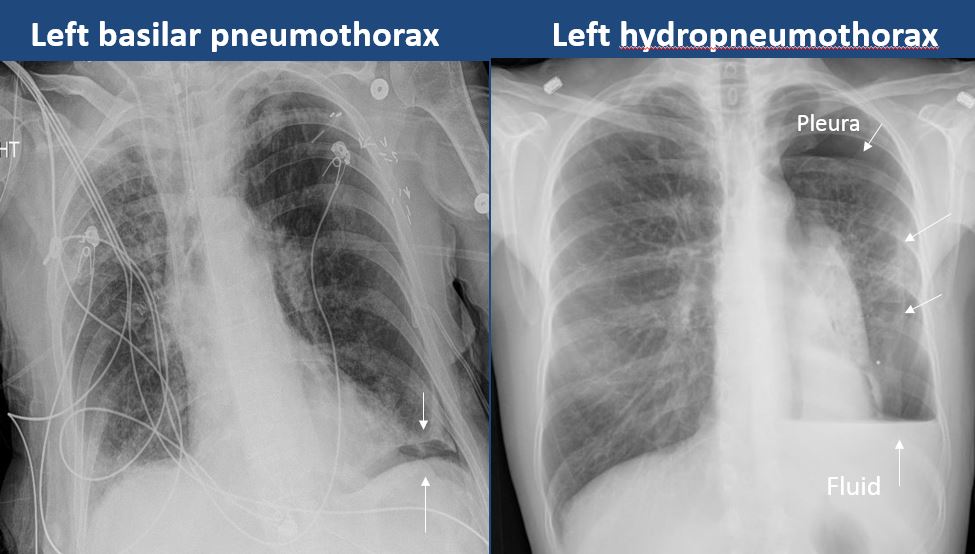

There is a pneumothorax, hydro/pneumothorax, or hemo/pneumothorax. |

no | NA |